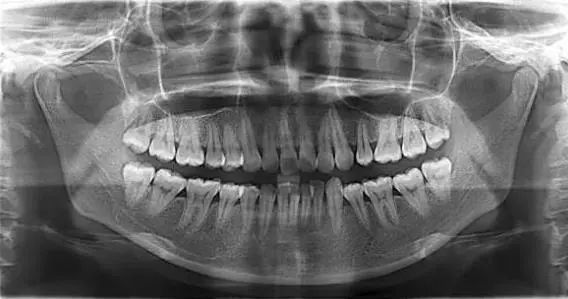

全景片 一次

全景片 (6岁以上) 一次

-韩国怡友vatech全景片-

用全景机为牙齿拍一张全景片,可将口腔内部所有细节清晰呈现在医生眼前,每颗牙齿的问题、骨骼的排列和轮廓,甚至连每一根血管和神经都清晰的毫发毕现,如同GPS定位系统一般,一切尽在医生掌握中。

这样极大加强了手术安全性、提升手术效果。